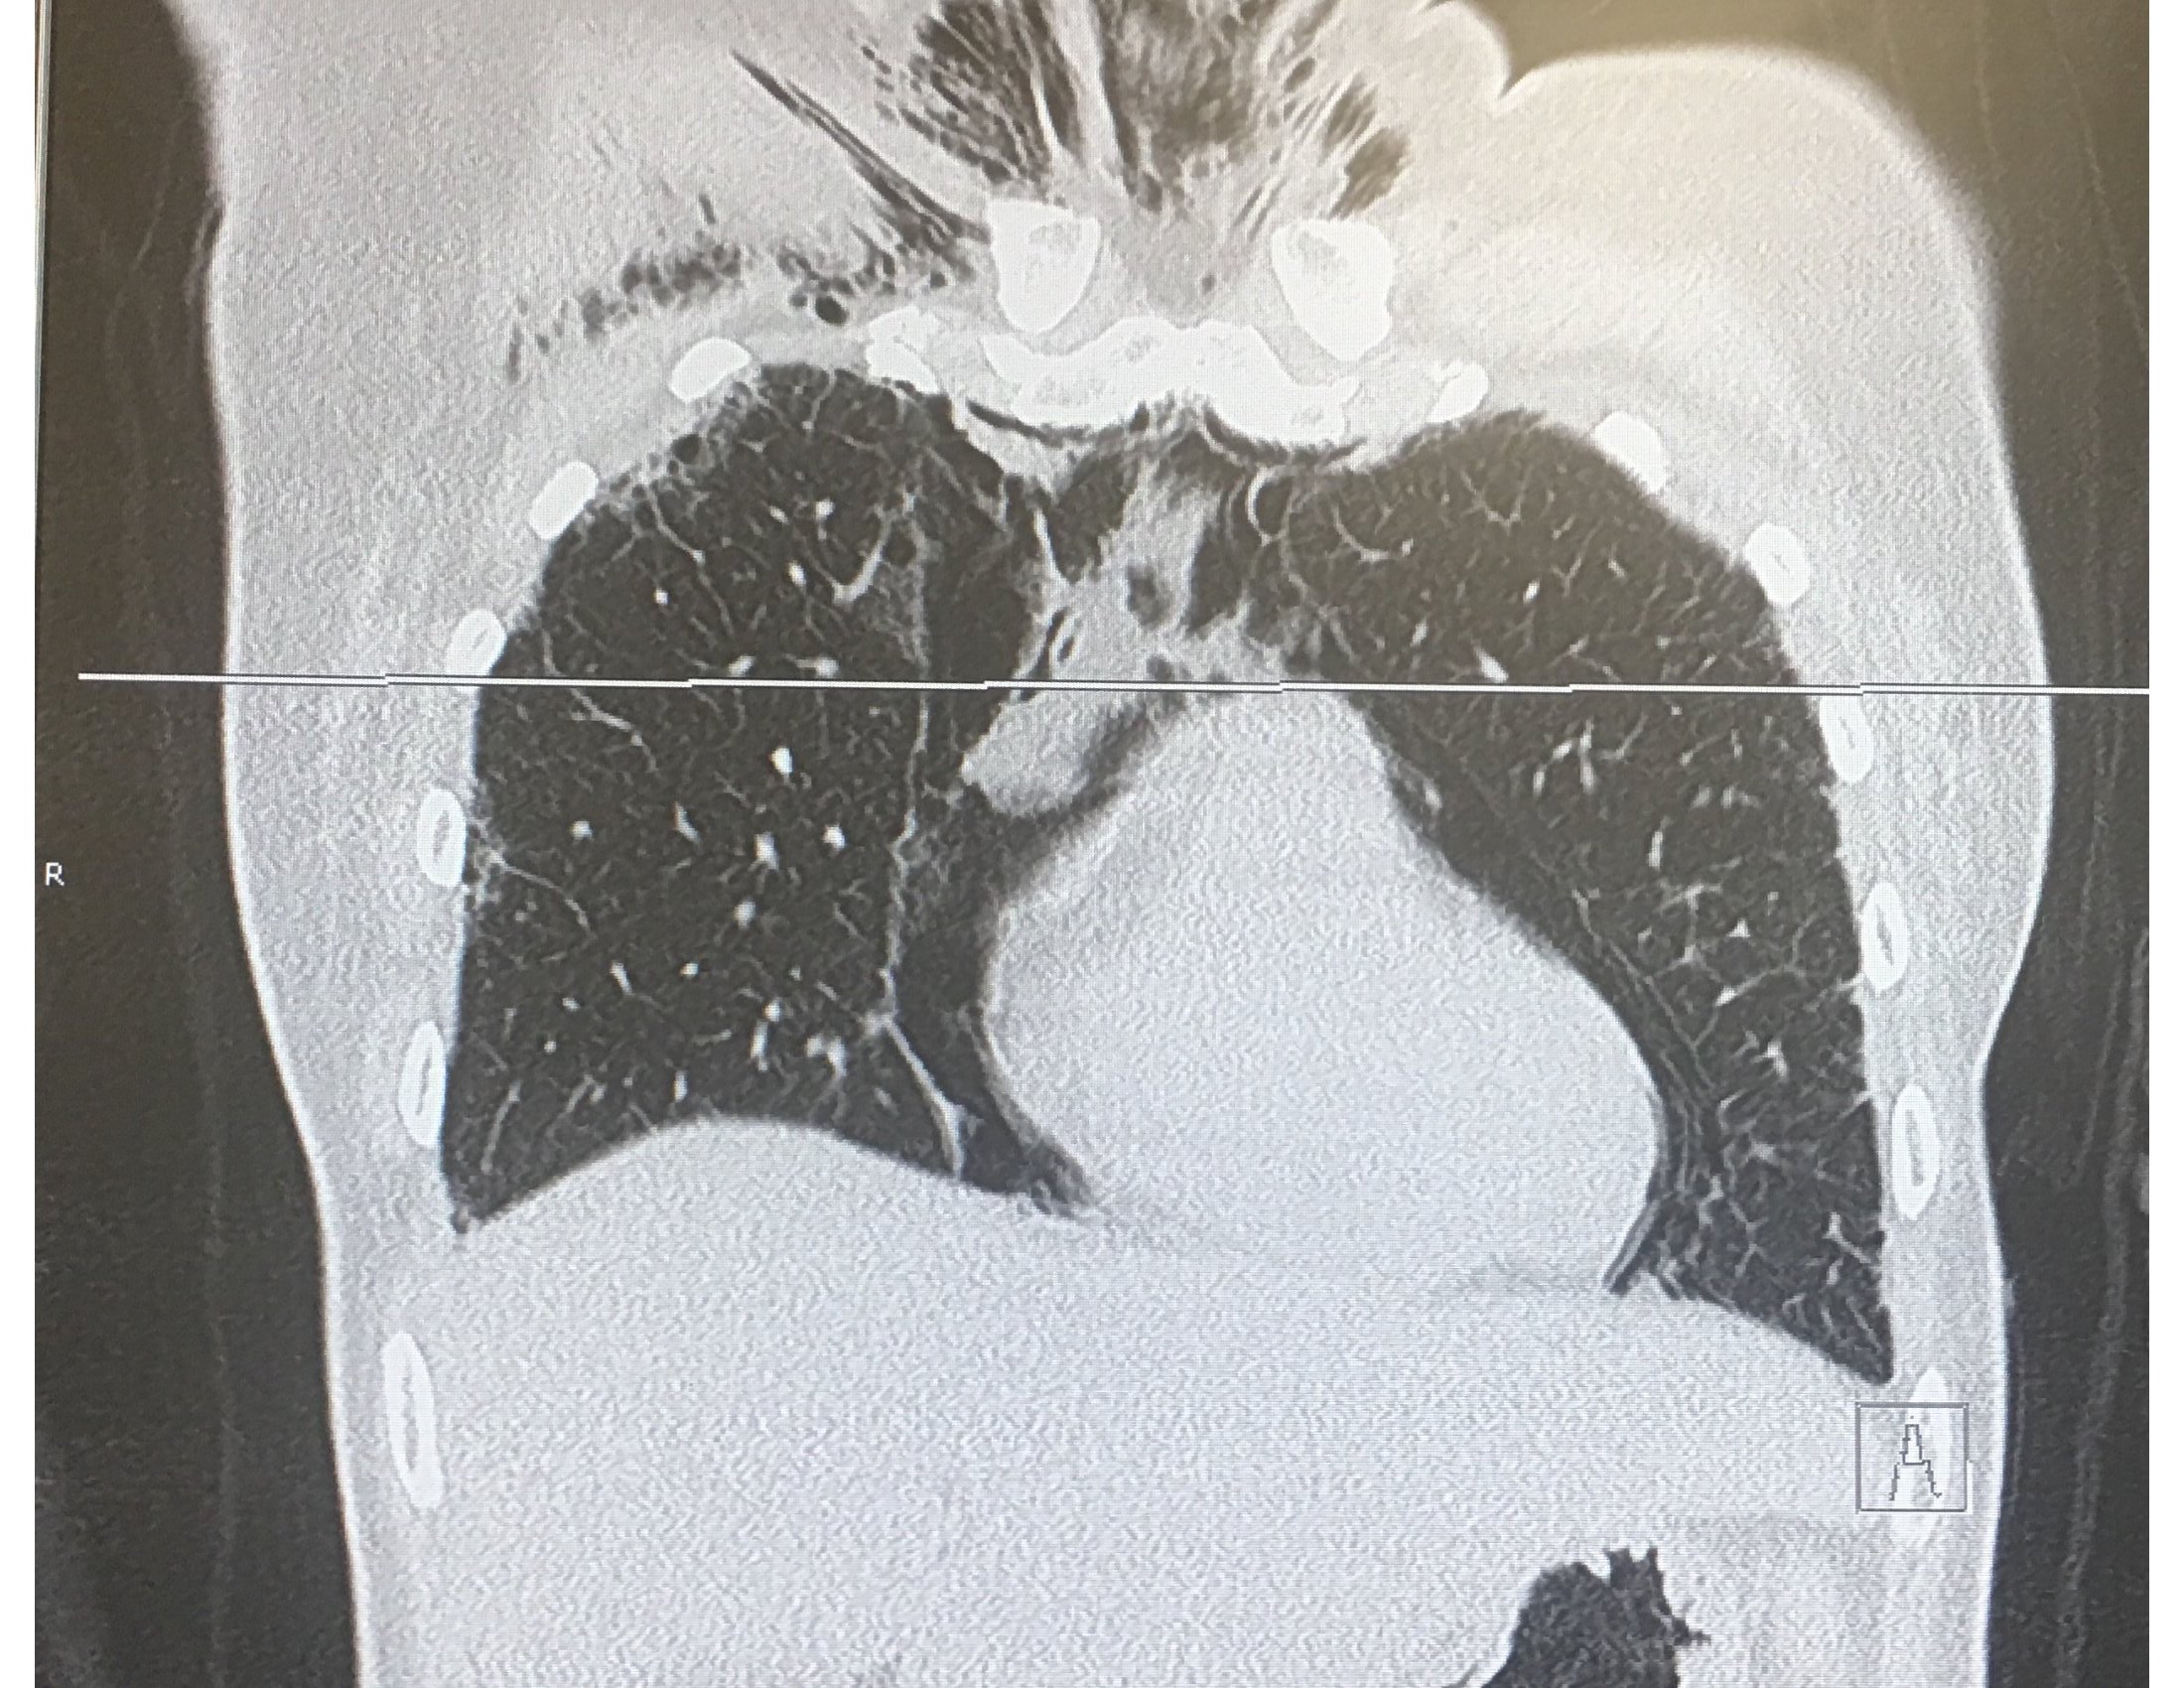

Case Presentation: A 33-year old female presented with 24 hours of subjective fever, severe neck, and chest pain. She was seen 6 months ago for arthralgia of the metacarpophalangeal, proximal interphalangeal and knee joints. Her home medication included Prednisone and Hydroxychloroquine prescribed for Lupus. Her physical examination demonstrated neck crepitus, bilateral crackles, ulcers in the tip of the fingers, erythroderma in elbows, knuckles and eyelids. CT chest revealed pneumomediastinum and right chest wall soft tissue emphysema. There were bilateral pneumothoraces and ground-glass opacities involving lower lobes bilaterally and bibasilar interlobar septal thickening. Laboratory data were significant for normal CPK levels. Anti-Jo1, PL-7, PL-12, Mi2, dsDNA antibodies were negative. ANA ab and Anti mitochondrial M2 were positive. O2 supplementation, Prednisone, Rituximab, and Mycophenolate were given since admission with marked improvement of the symptoms. Upon discharge, she was seen by her rheumatologist who diagnosed Antisynthetase syndrome after new laboratories were ordered.

Discussion: Antisynthetase syndrome is a very uncommon disease, with a reported annual incidence of two new cases per one million adults. This is probably an underestimation caused by a lack of familiarity with this syndrome which criteria were described less than ten years ago. Connor’s criteria include the presence of antibodies against aminoacyl t-RNA synthetase along with features of interstitial lung disease, myositis, Raynaud’s phenomenon, and arthritis. Anti-histidyl antibody (Jo-1) is the most commonly detected antibody (30%).Clinical features of this patient including interstitial lung disease, Goitron papules, mechanical hands, and polyarthritis suggested Antisynthetase syndrome. Imaging studies supported the diagnosis because common findings reported in the literature include ground-glass opacities and interlobar septal thickening as seen in this patient. However, this is a challenging scenario because the patient did not meet diagnostic criteria due to a lack of specific antibodies. This could be explained by autoantibody levels fluctuation depending on disease activity. Also, only a few aminoacyl transfer RNA synthetase antibodies have been identified, many are still not available for laboratory detection.In terms of treatment, there are not clinical trials due to the rarity of this condition. However, cases reported indicating that high dose steroids are the most effective medication in controlling acute pulmonary disease associated with this syndrome. They are used in combination with mycophenolate, and rituximab to improve the prognosis. Complications like spontaneous pneumothorax are managed with oxygen and supportive therapy on stable patients.